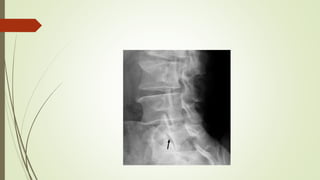

 X-RAY

shows :

“ SCOTTISH DOG SIGN”

DIAGNOSTIC PROCEDURE  SPECT(single photon emission computed tomography) shows area of involvement  X-ray shows area of involvement

 X-RAY shows : “SCOTTISH DOG SIGN”